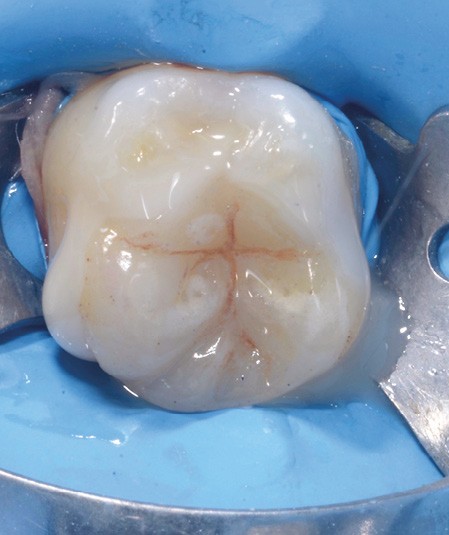

Lors de la préparation d’une cavité pour inlay/onlay, il est fréquent d’être confronté, en fin de nettoyage, à la présence d’une ou plusieurs parois résiduelles dont la résistance mécanique paraît douteuse du fait de leur localisation ou de leur épaisseur. Les parois épaisses (+ de 2 mm) peuvent généralement être conservées (cas clinique 1) et les parois fines (- de 1 mm) doivent généralement être recouvertes. Un inlay (en composite ou en céramique) est alors réalisé. Il doit avoir lui même, au final, une épaisseur globale minimale de 2 mm pour assurer sa résistance mécanique intrinsèque à la mastication. Si un recouvrement cuspidien est indiqué, la réduction occlusale doit donc se faire sur 2 mm de hauteur au minimum [1, 2].

S’il est impossible de connaître avec certitude le risque de fracture d’une cuspide, l’objectif de cet article est de donner des éléments objectifs de prise de décision de la conservation ou du recouvrement des parois d’épaisseur moyenne à la fin du nettoyage cavitaire selon la dent, l’occlusion, la forme et le volume de la cavité, la présence ou non de dentine, la vitalité ainsi que l’incidence esthétique.